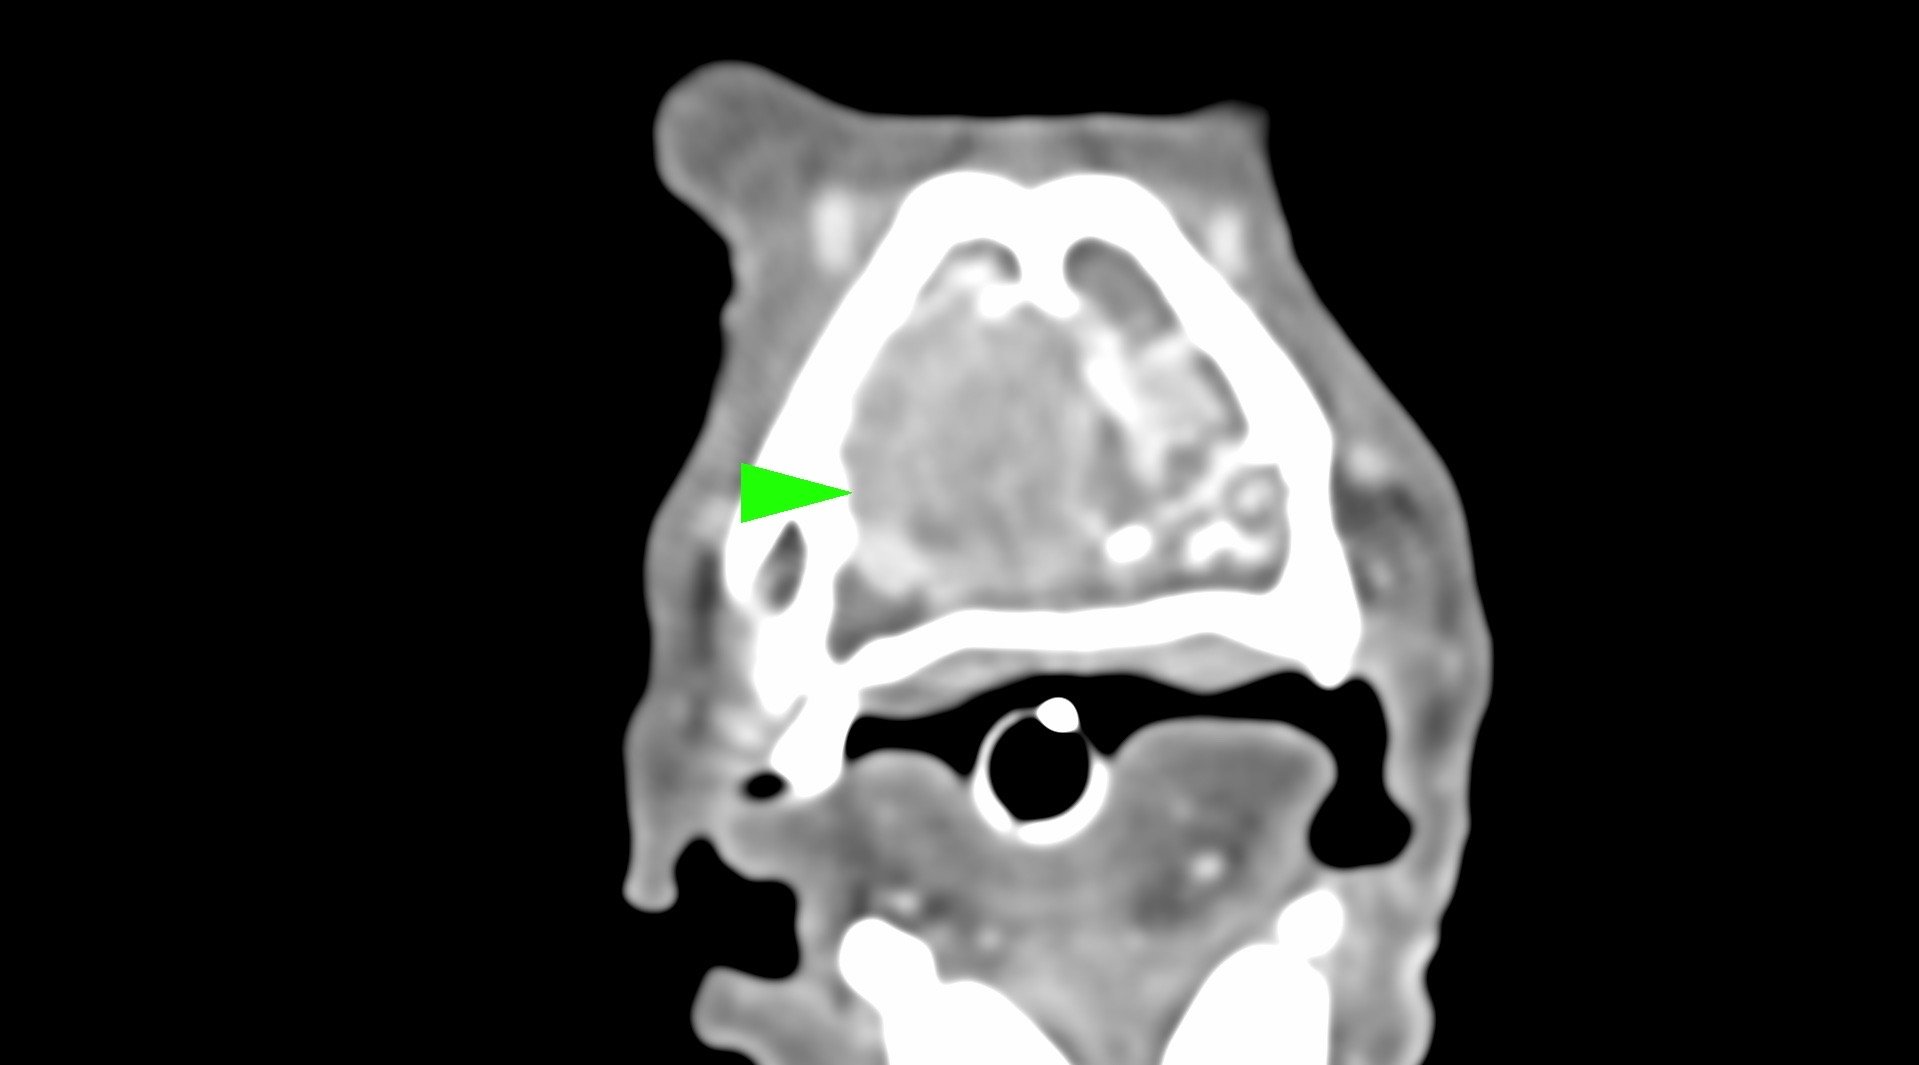

鼻腔症狀是門診中狗貓最常見的主訴之一,但在診斷上卻不那麼容易,在缺乏如電腦斷層、內視鏡、牙科X光等特定設備的情況下,門診醫師多只能嘗試性的給藥觀察,對於慢性、頑固、難治的鼻腔問題往往便束手無策了。

柴犬皮皮因長期有鼻塞、流鼻血、流鼻水的症狀來築心就診,在這之前已經換過兩間醫院,但治療效果都不太好。在一系列的評估後,我們為皮皮安排了電腦斷層以及鼻腔內視鏡的檢查,檢查後發現在皮皮的鼻腔內有疑似腫瘤的團塊,並且向後侵入鼻竇,甚至已經接近大腦。我們運用內視鏡設備採樣取得了團塊的切片,並得到鼻上皮細胞癌的診斷。